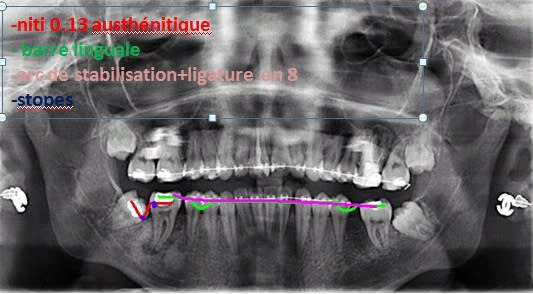

Le plus simple est d'en utiliser une courte qu'on placera dans le bord antérieur de la branche montante après l'avoir enfilée dans l'anneau d'une ligature qui émergera, elle, en distal de la molaire. Voir planche photo jointe.

Redress molaire f7uszx - Eugenol